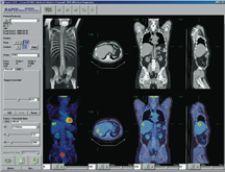

C4’s PET/CT plug-in displays images and information in a PACS-like reading context across dual monitors. “Radiologists reporting PET/CT cases are often looking for information and functionality beyond the capabilities of a standard PACS workstation. Capabilities such as image registration, image fusion, hot spot analysis and SUV are particular to PET/CT imaging. With C4 however, this functionality can be incorporated into a standard PACS workstation,” explained Clark. “In this example, the workflow value of C4 is fairly clear – a radiologist does not need to move from a PACS reporting workstation to a separate PET/CT workstation. Comprehensive diagnostic support can be provided on any PACS workstation throughout the healthcare enterprise. One can similarly see how this technology benefits a radiologist working in areas that require five or six different clinical applications to be used regularly.”

In anticipation of all specialty imaging workstations requiring PACS, HIS, 3-D tools, remote access and interoperability with other departments, physicians and hospitals, HERMES has developed RAPID CD, an application for the display and analysis of PET, NM, CT, MRI and ultrasound exams. Designed for users who do not have direct access to an image server, it features image fusion capability, shows three orthogonal views simultaneously across modalities, has image reorientation, MIP movie data, splash display, volume of interest (VOI) generation and standard uptake value (SUV) calculation, and can be used on a PC.

“The solution is very intuitive and enables us to import several 3-D image sets on the HERMES workstation,” indicated Treves. “The ability of the system to communicate with the PACS helps with the efficiency of the image fusion process. So one can say for this patient, I would like to import the CT and the SPECT, or to import the MRI and the PET. The system allows you to bring these image sets into the HERMES workstation very easily and then proceed with the image fusion. Results become available within a clinically useful time. Image fusion now takes a few seconds. In the past, it took up to an hour or two hours.”